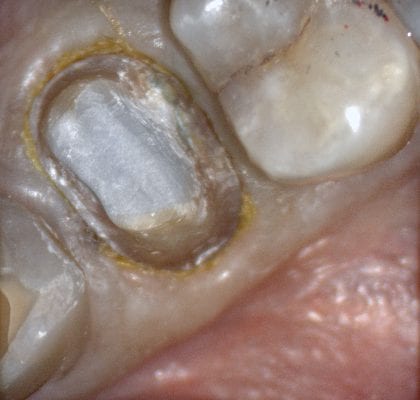

Immediate Post Op

The remaining decay and previous build up material was removed just prior to bonding the restoration with NX3 dual cure resin cement so the dentin was exposed for the least amount of time possible.